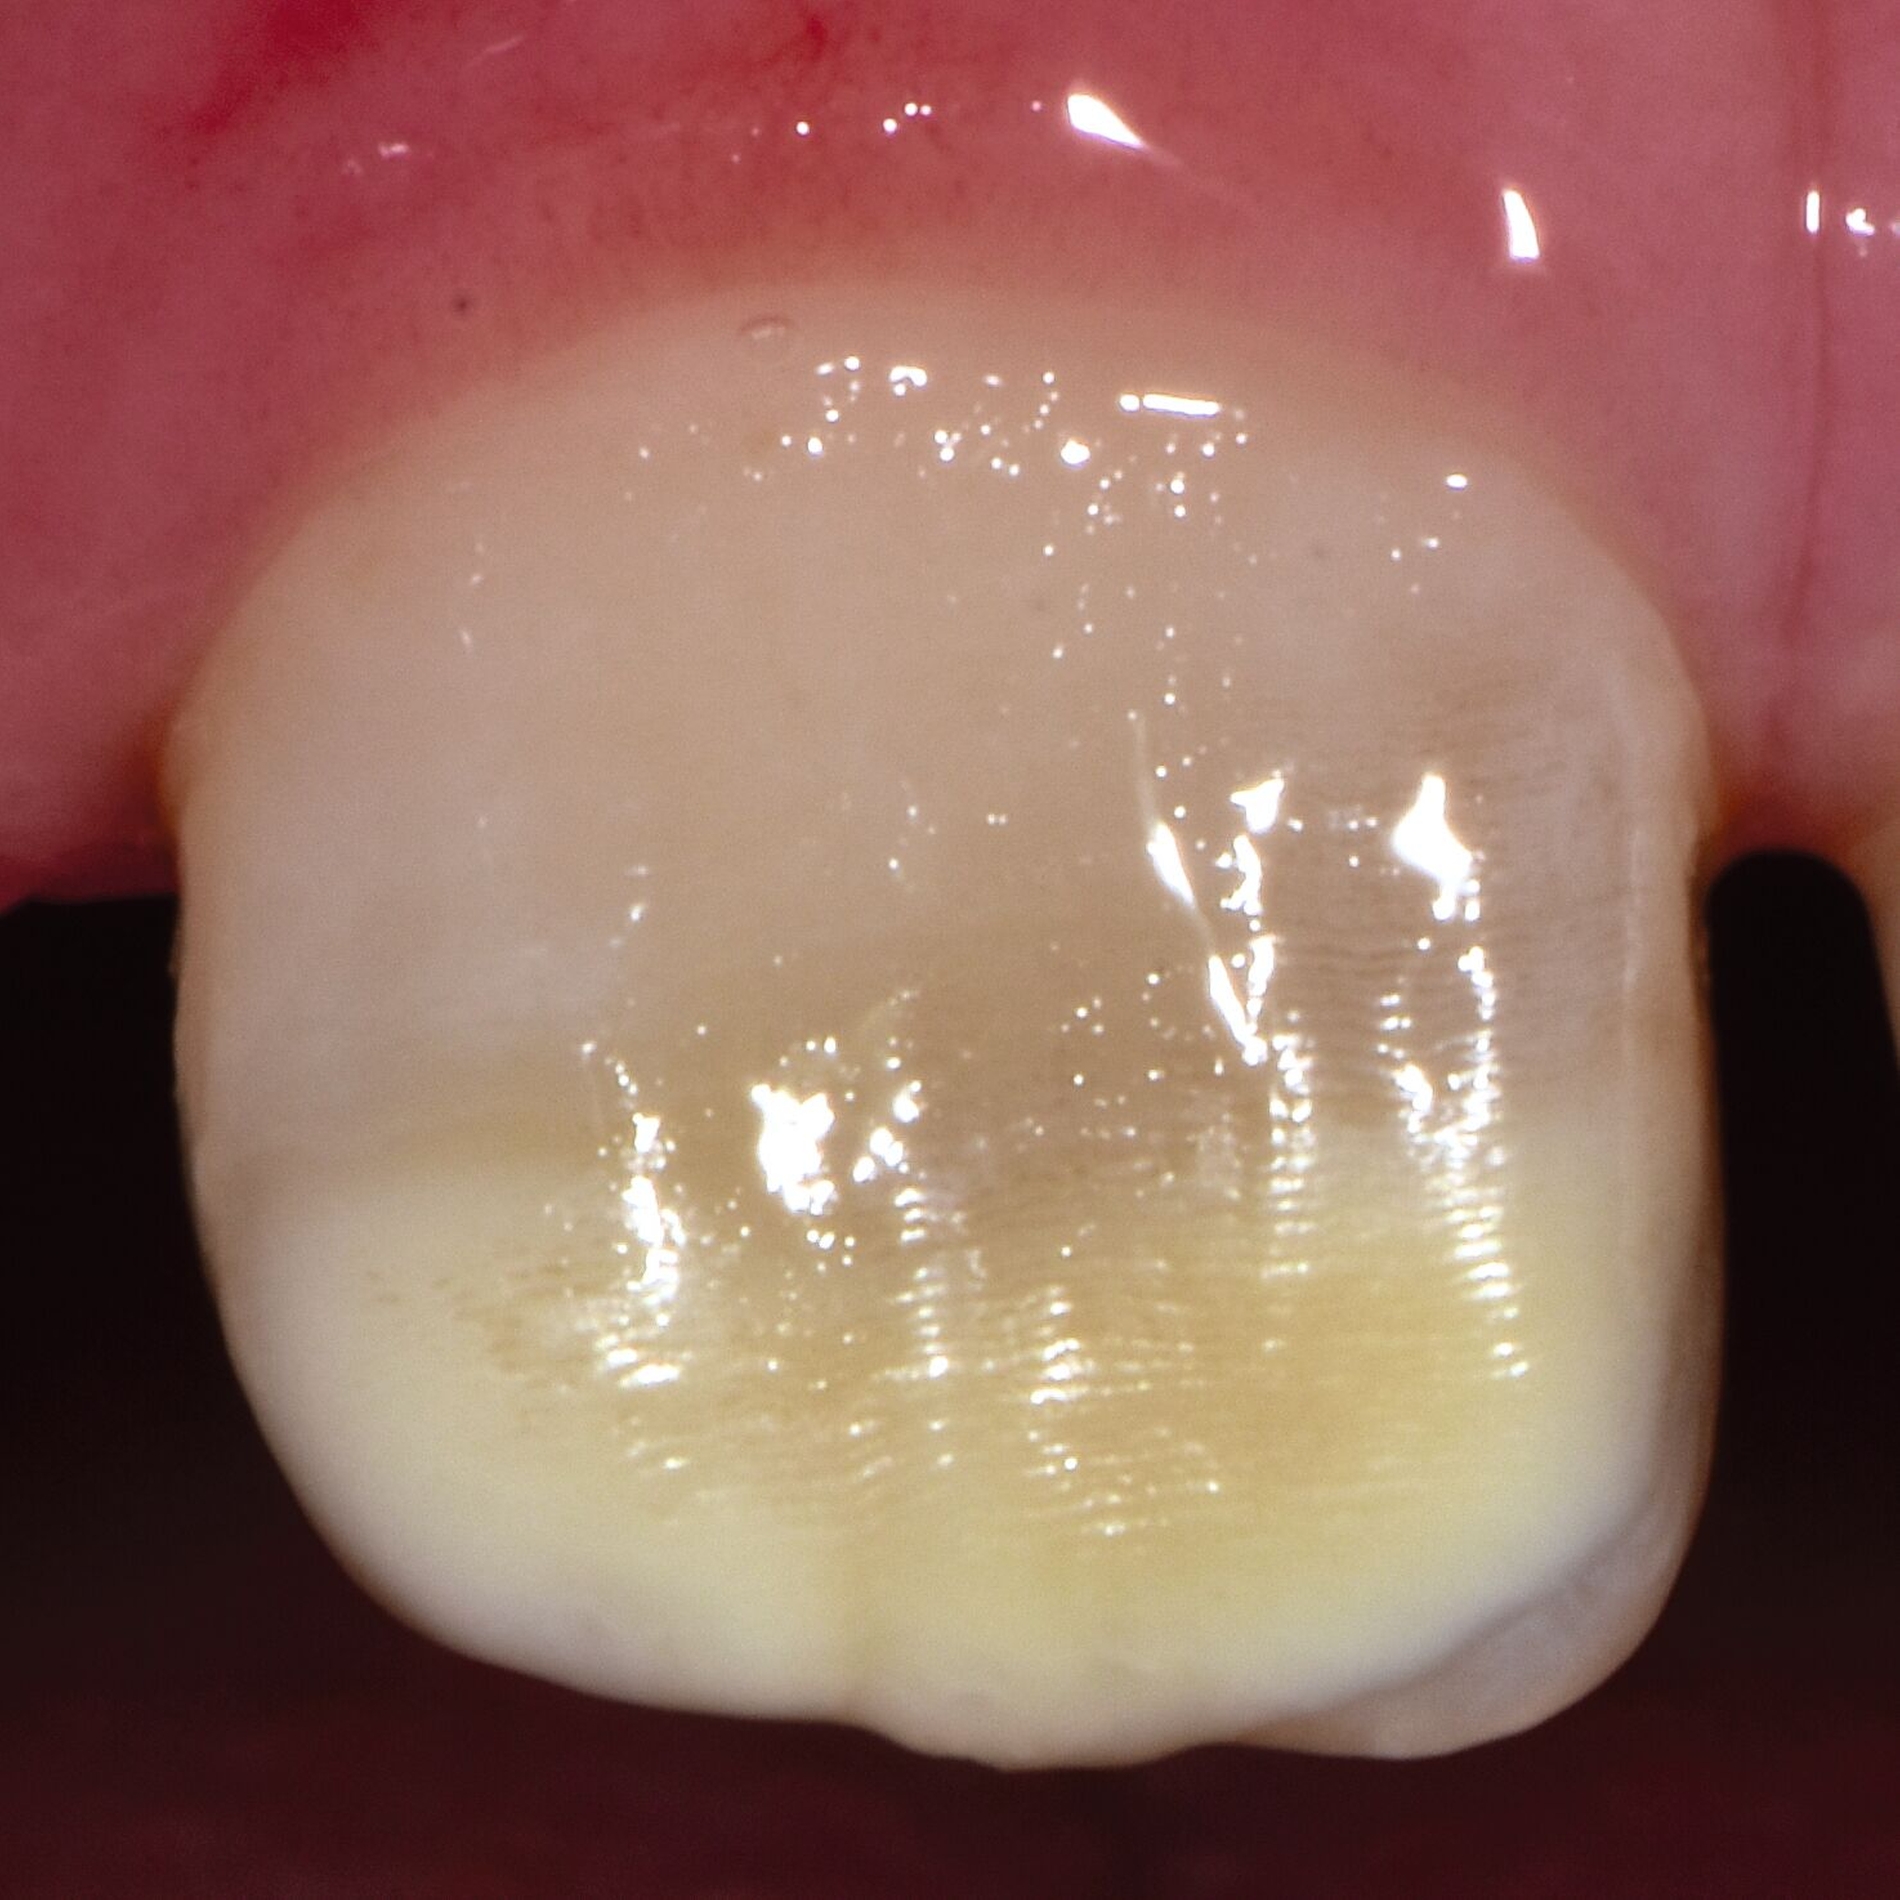

Das klinische Erscheinungsbild an bleibenden Zähnen zeigt typischerweise weißlich-gelbe bis gelblich-braune Opazitäten, die zumindest in einigen Bereichen durch eine scharfe Abgrenzung (engl.:„demarcated opacities“) zum gesunden Zahnschmelz charakterisiert sind (Abbildungen 3 und 4). Die abgegrenzten Hypomineralisationen befinden sich mehrheitlich im Bereich der inzisalen Kronenhälfte unabhängig von dem Auftreten an Front- oder Seitenzähnen. Die Ausprägung am Zahn kann dabei auf einzelne Areale oder Höcker begrenzt sein.

Bei einer schwerwiegenderen Ausprägung sind Zahnflächen vollständig betroffen, mitunter alle Zahnflächen an einem Zahn. Die Verteilung in der Dentition beziehungsweise an den Indexzähnen ist gleichermaßen variabel und betrifft nicht nur die Defektgröße, sondern auch die Farbe und Festigkeit. Was die Festigkeit betrifft, gilt als die Faustregel: Je dunkler die Farbe des Schmelzes, umso weicher beziehungsweise poröser und damit minderwertiger wird dessen Qualität sein. Damit reduziert sich seine kaufunktionelle Belastungsfähigkeit, was insbesondere an ersten bleibenden Molaren von klinischer Relevanz ist.

Für die Dokumentation und Klassifikation der MIH wurden verschiedene Systeme vorgeschlagen. Als historisch und veraltet gilt der (modifizierte) DDE-Index. Demgegenüber haben die Kriterien der EAPD – abgegrenzte Opazitäten (Abbildung 3 und 4), Schmelzeinbrüche (Abbildung 5), atypische Restaurationen (Abbildung 6) – mittlerweile die weiteste Verbreitung gefunden. Diese wurden 2003 erstmals zur Beschreibung der MIH auf empirischer Basis publiziert [Weerheijm et al., 2003] und den Jahren 2010 und 2022 im Rahmen der damaligen MIH-Workshops bestätigt [Lygidakis et al., 2010; 2022].